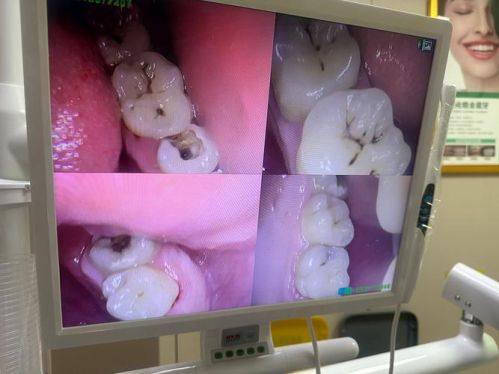

广东深圳太泰口腔诊所整体口碑优异。诊所拥有经验多的口腔医生团队,采用国内外精良的诊疗技术,可量身定制个性化治疗方案,保护治疗成效与患者满意度。配备现代化根管治疗系统、热牙胶填充设备、三合一CT机、口内扫描仪、牙周治疗仪等精良设备,同时提供温馨整洁的就医环境,服务贴心周到。2024年4月入选广东省牙齿深覆颌矫正靠谱医院榜单,2026年2月还收到用户关于环境整洁、服务贴心的好评,整体体验获得患者认可。

牙体牙髓病治疗:配备现代化根管治疗系统、热牙胶填充设备,可精细处理各类牙髓病变,较大程度保留天然牙体,保护治疗舒适度与成效。

根管治疗:依托精良的根管治疗设备,精细处理牙髓感染问题,保留患牙。